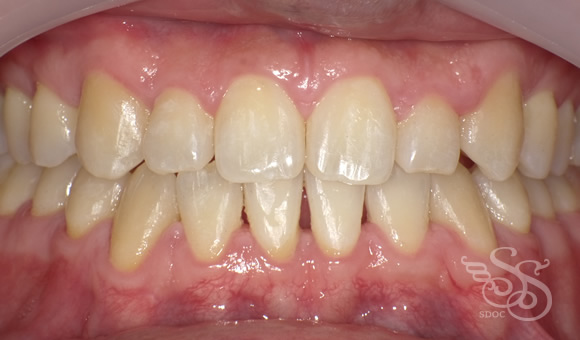

正面:術前

正面:術後